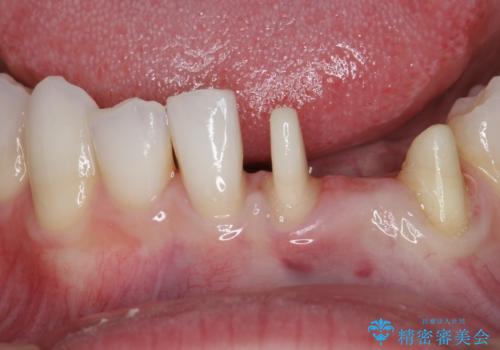

- 他院にて矯正治療を行ったが、左下の前歯の見た目が気になるのでセラミックで治したいといらっしゃった方の症例です。

左下123番のブリッジになるが、左下1番と3番の歯軸が合っておらず神経治療が必要になる可能性があるため部分矯正を提案したところ、希望されなかったため、そのままの歯軸でオールセラミッククラウンによる補綴を行いました。